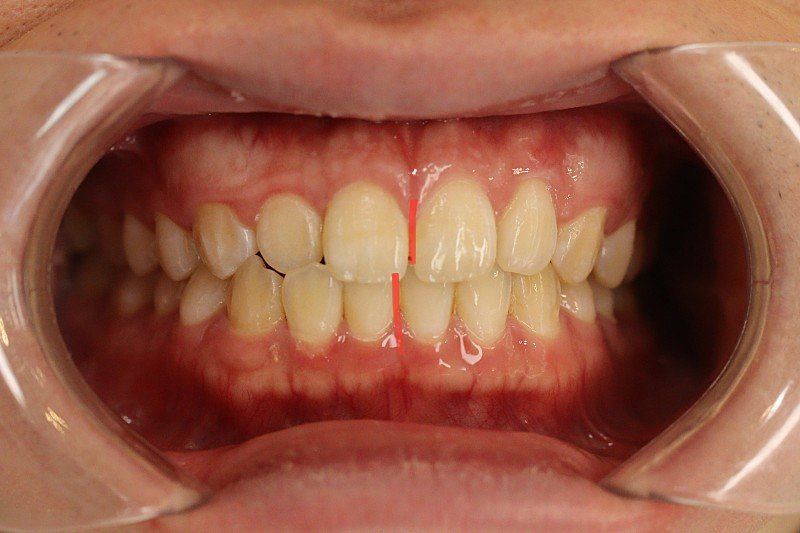

)치아 뼈가 전방으로 많이 나온 상태인가요?

)골격적으로 나온건가요?

1. 전방으로 많이 나왔다고 볼 수도 있지만 심미적으로 봤을 때 치료를 하지 않아도 되는 정도입니다. 본인이 현재 안모에 불만족스럽다면 이는 치료의 대상입니다.

2. 해당 정도로는 교정으로 개선이 불가능하며 양악을 하셔야 합니다.

3. 돌출입이 있다고 해서 무조건 구호흡이 나타나는 것은 아니나 돌출입이 원인이 되어 현재의 증상을 악화시킬 수도 있습니다.